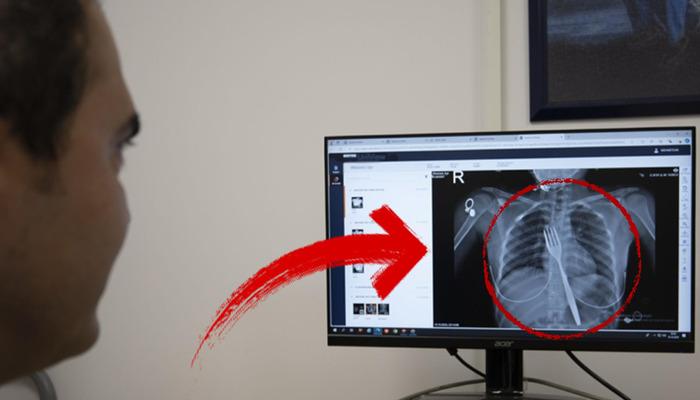

Söke’de ikamet eden yabancı uyruklu EE (18), çatal yutma şikayetiyle ambulansla Aydın Adnan Menderes Üniversitesi Hastanesi’ne (ADÜ) götürüldü. Burada röntgeni çekilen hastanın yemek borusunda 18 santimetrelik çatal olduğu belirlendi.

Uzmanlar endoskopi yaparak çatalı ağızdan çıkarmaya çalıştı. Ancak yemeğe ve nefes borusuna zarar verme ihtimali nedeniyle midenin kesilip çatalın çıkarılmasına karar verildi.

ADÜ Tıp Fakültesi Göğüs Cerrahisi Anabilim Dalı Öğretim Üyesi Dr. Salih Çokpınar ve Genel Cerrahi Anabilim Dalı Dr. Öğretim Üyesi Akay Edizsoy’un koordine ettiği operasyonda midede kesi yapılarak çatal çıkarıldı.

Edizsoy, vakayı ilk duyduğunda şaşırdığını belirterek, şöyle konuştu: “Büyük bir çatalın tamamen yutulması sonucu oluşan bu vakayı ilk duyduğumda doğru olmadığını düşünmüştüm. Hasta 18 yaşında ve 18 yaşındaydı. Yabancı uyruklu. Türkçesi biraz zayıf olduğu için bir yanlış anlaşılma olabileceğini düşündük ama hastayı çektiğimizde aslında çatal yutuyordu.” “Yemek borusunda olduğunu gördük.” dedi.

“Bu yüzden çok endişelendik. Ancak endoskopide ciddi bir lezyonun olmadığını gördük. Oldukça büyük olduğundan ve endoskopik aletlere uygun olmadığından endoskopi ile çıkarılamadı. Büyük bir masa çatalı olduğu için kendine ait. ağırlıktır. Bir çivi gibidir, bir iğne gibidir. “Tutulamaz ve çıkarılamaz. Bu nedenle karından kesi yaparak mideye ulaşıp midenin içinden çıkarma stratejisi izledik. Bu ameliyatla bu çatalı oradan çıkarmayı başardık.”